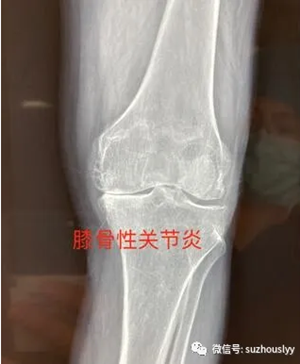

患者高某,67岁,膝关节反复疼痛、行走不便多年,重度骨性关节炎表现,长期保守治疗,效果欠佳。由于膝关节疼痛行走不便,患者不慎摔倒,拍片显示髌骨粉碎骨折,随即收住我院骨一关节科接受住院治疗。

术前片子显示骨性关节炎